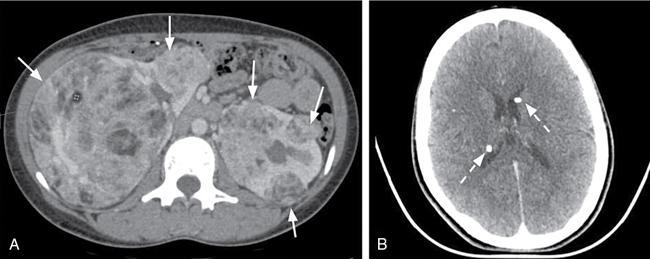

Naren Hemachandran, Devasenathipathy Kandasamy, Geetika Khanna Renal neoplasms are rare in children, accounting for less than 10% of childhood cancers. Nonneoplastic conditions like hydronephrosis, hypertrophied column of Bertin, foetal lobulations, calyceal diverticulum, simple renal cyst and infective causes like acute pyelonephritis, renal abscess can present as a renal mass clinically or on imaging. These nonneoplastic conditions are more common than true neoplasms in the early infantile period and radiologists should be aware of these conditions to avoid misdiagnosing them as neoplasms. In this chapter, we describe a clinic-radiological algorithmic approach as well as review the common paediatric renal neoplasms. Renal neoplasms can present as abdominal distension, mass palpable per abdomen (commonly detected by parents while bathing a child), flank pain, haematuria or rarely with other atypical symptoms. Imaging plays an important role in the detection, characterization, preoperative staging, image guided sampling, treatment planning and posttreatment follow-up or surveillance. Ultrasonography is the initial modality for detection as well as characterizing a mass as solid or cystic. This differentiation plays an important role in characterizing renal masses in children as further elaborated in this chapter. Computed Tomography (CT) is the preferred modality for further evaluation due to high spatial and temporal resolution and short scan times. In addition, CT allows for simultaneous evaluation for lung metastasis, a critical part of staging. Due to the need of sedation or general anaesthesia because of the longer acquisition time, Magnetic Resonance Imaging (MRI) is primarily used as a problem-solving tool and for evaluation of bilateral renal neoplasms. The characterization of renal masses in children may not always be possible by imaging due to significant overlap in the imaging and clinical features. In this chapter, we propose a radiological algorithm for the characterization of various renal masses in children. This is based on the primary nature of the mass and they are classified into predominantly fat containing, predominantly cystic and predominantly solid groups (Fig. 10.9.1). Predominantly solid masses are further subclassified based on the age at presentation. Various neoplasms have been categorized into these groups based on the most typical findings. This radiological algorithm is not absolute but intends to provide a practical approach to narrow down the differential diagnosis in a child with a renal mass. Angiomyolipoma is the most common fat-containing renal neoplasm in children. Other lesions like renal cell carcinoma, Wilms’ tumour also can show fat within. However, in such cases, fat component is seen along with other solid/cystic components and these do not present as predominantly fat containing and hence are described elsewhere. Angiomyolipomas are benign neoplasms and are composed of varying amounts of dysmorphic blood vessels, smooth muscle and fatty elements. In the adult population, the majority of them are sporadic, while the remaining 20% are seen in association with tuberous sclerosis. However, in children, the majority of the detected lesions are seen in association with tuberous sclerosis. The presentation varies with the size of the lesion. Small angiomyolipomas are typically detected during screening/annual surveillance of children with tuberous sclerosis. Those more than 4 cm are more likely to undergo spontaneous haemorrhage and present with pain, haematuria or rarely with life-threatening retroperitoneal or subcapsular haemorrhage. Although they are benign neoplasms, rarely they can show extension into the renal vein and subsequently into the inferior vena cava. On imaging, identification of a predominantly fat-containing mass enables us to confidently diagnose an angiomyolipoma (Fig. 10.9.2). However, there can be significant variation in the amount of fat within the lesion and some authors classify them into fat rich and fat poor angiomyolipomas. The fat can be either macroscopic fat or microscopic fat. The imaging features vary depending on the fat content. On ultrasonography, they are usually hyperechoic. The degree of heterogeneity of the lesion and the vascularity increases with increase in size of the lesion. Intratumoural prominent vessels, vascular lakes and pseudoaneurysms are well demonstrated on colour Doppler. CT is very helpful for the detection of the macroscopic fat even in smaller lesions. MRI helps in the demonstration of microscopic fat using chemical shift imaging, in which microscopic fat shows typical drop in signal intensity in opposed-phase images compared to in-phase images. Dixon technique is also very well suited for detection of small fat-containing angiomyolipomas, as the small foci of fat are very conspicuous on fat only images. The most common lesions that show predominant cystic areas on imaging are multilocular cystic nephroma, cystic partially differentiated nephroblastoma (CPDN)/cystic Wilms’ tumour. Previously these three tumours were considered to be along the same continuum with increasing blastemal components in CPDN compared to cystic nephroma, though recent studies have shown that these are distinct clinical/pathological entities. Multilocular cystic nephroma is a benign neoplasm more commonly seen in young boys. On sonography it appears as multiloculated cystic lesions with multiple thin septae within. The walls of the cyst and the septae show smooth thin enhancement on postcontrast imaging with no nodular or solid enhancing areas. The microcystic type can artifactually appear solid on imaging. These tumours typically present as Bosniak 3, and less commonly as Bosniak 2 renal cysts. Herniation into the collecting system is a characteristic finding, although it is not always seen (Fig. 10.9.3). Recent studies have shown a strong association of multilocular cystic nephroma with DICER-1 mutation. The lungs should be evaluated in these children for associated cystic lesions which can represent pleuropulmonary blastomas. The presence of solid enhancing component within a predominantly cystic lesion or nodular enhancement along the septae of a cystic lesion point towards a diagnosis of cystic Wilms’ tumour. Clinical, demographic features and the response to chemotherapeutic agents are similar to that of Wilms’ tumour, which is considered in detail in the next section. Most of the renal neoplasms in children are predominantly solid with significant overlap of imaging and clinical features. There are some typical features which are however, not seen always. We have further divided the predominantly solid masses based on the mean age of presentation of the lesions. This approach is not infallible, due to the wide range of the age of presentation of these lesions, and only aims to provide a practical working algorithm. Many times, even after the best of the efforts, it is impossible to pinpoint to a specific diagnosis and histopathology is needed to make the final diagnosis. Mesoblastic nephroma is the most common solid renal tumour in neonates. It was originally thought to represent congenital Wilms’ tumour. However, Bolande et al. in the late 1960s first described it as a separate entity and since then has been recognized as a distinct entity. It is also called as foetal renal hamartoma or leiomyomatous hamartoma. Mesoblastic nephroma typically presents in the first few months of life though it may be detected in utero on routine antenatal ultrasound or MRI studies. It shows a male preponderance. There are two histologic subtypes – classical and cellular types. The classical type shows features similar to that of uterine leiomyoma and is homogeneous with a whorled appearance. The cellular type tends to be larger, crosses the midline more often and occurs in slightly older patients (>3 months of age). Both the subtypes are unencapsulated but the cellular subtype shows a ‘pushing’ border with the adjacent kidney. The cellular type shows a multiseptated appearance with haemorrhage, necrosis and cystic areas resulting in a heterogeneous appearance (Fig. 10.9.4). Cellular mesoblastic nephroma tends to be more aggressive than classic. Calcification is rare and the absence of calcification is an important finding to differentiate it from the other common lesions seen in infants.